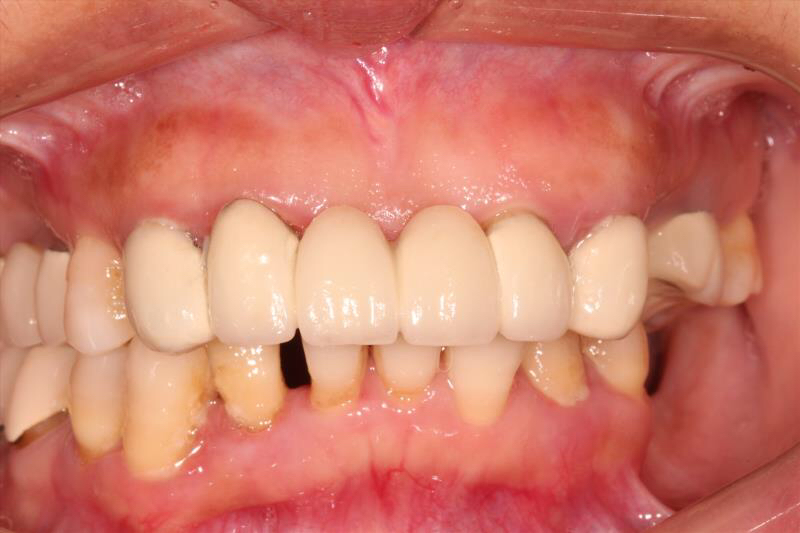

患者中年女性,左下5、6、7缺失多年,牙槽骨吸收较多,CBCT可见牙槽骨高度不足,距离下颌神经管比较近,所以为这位患者选择了短植体进行种植,术中植骨盖膜,历时7个月戴上了牙齿,患者使用满意。